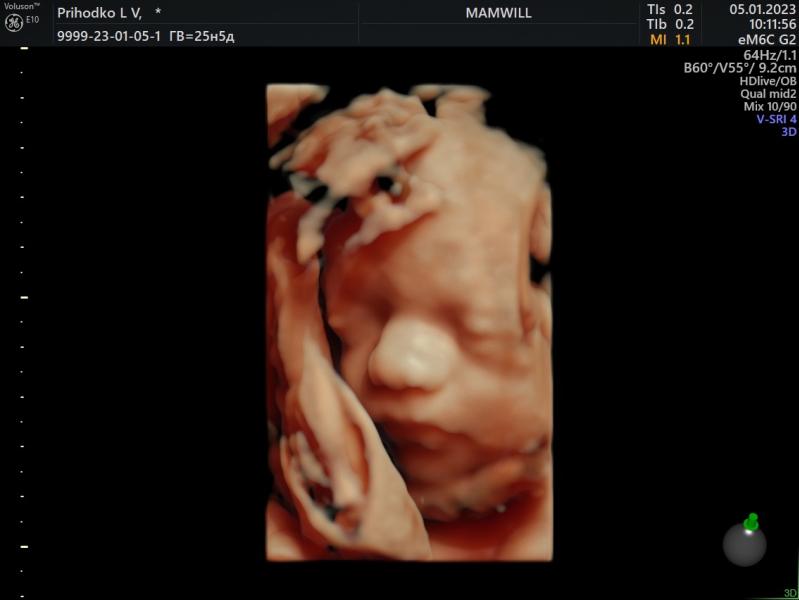

Наш долгожданный🤍

Были сегодня на встрече с мужем 🥰

Весит наш малыш 789 грамм

Сидим пока на попе с ногами на голове🙂

п.с. В конце его обидели уже🤧

05.01.2023